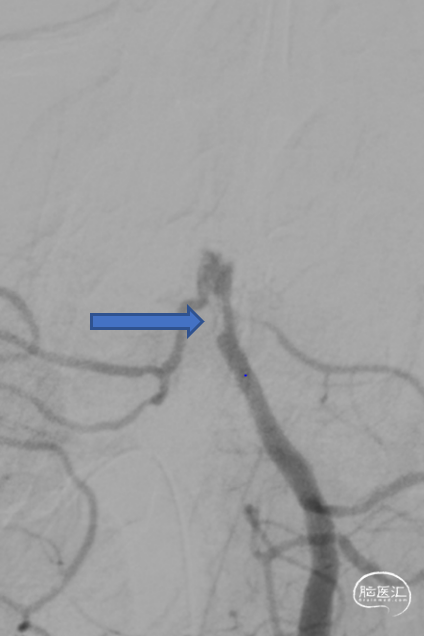

第一次取栓后,血管未通,但明确支架内狭窄位置,交换引入头端塑形的300cm 0.014in微导丝,撤出微导管,沿微导丝引入2.0mm*15mm Sprinter球囊,扩张后狭窄明显减轻,但血栓掉落至右侧大脑后动脉起始部。

交换再次引入加奇4.0mm*30mm Syphonet®取栓支架并释放。